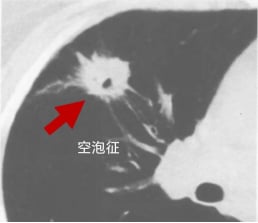

三、空泡征:结节内的“小气泡”

空泡征是指在肺结节内部出现直径小于5mm的气体密度影或低密度影,可单个或多个存在,且在相邻两个以上层面不易连续观察到。这些“小气泡”的形成可能与未被肿瘤完全占据的含气肺组织、未闭合或扩张的小支气管、乳头状癌结构间的含气腔隙,以及肿瘤内小灶性坏死排出后形成的空洞有关。研究表明,空泡征在肺癌中的出现率显著高于良性结节(28.7% vs 8.2%),尤其在肺泡癌、腺癌和鳞癌中更为常见,是鉴别恶性肺结节的重要依据。